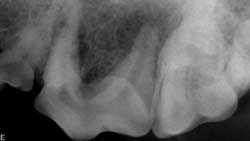

Definitive DiagnosisDental radiographs are obtained to determine or verify which tooth is affected. The affected tooth root will have a periapical lucency around the apex (Figures 3 through 5. View larger image), indicating bone loss.

Multiple views may be required to confirm which tooth is involved, especially when trying to distinguish between an infected maxillary 4th premolar and 1st molar.